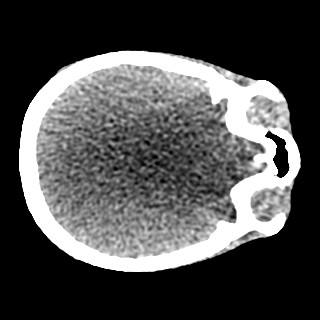

Cone-beam CT (CBCT) employs a flat-panel detector to achieve three-dimensional imaging with high spatial resolution. However, CBCT is susceptible to scatter during data acquisition, which introduces CT value bias and reduced tissue contrast in the reconstructed images, ultimately degrading diagnostic accuracy. To address this issue, we propose a deep learning-based scatter artifact correction method inspired by physical prior knowledge. Leveraging the fact that the observed point scatter probability density distribution exhibits rotational symmetry in the projection domain. The method uses Gaussian Radial Basis Functions (RBF) to model the point scatter function and embeds it into the Kolmogorov-Arnold Networks (KAN) layer, which provides efficient nonlinear mapping capabilities for learning high-dimensional scatter features. By incorporating the physical characteristics of the scattered photon distribution together with the complex function mapping capacity of KAN, the model improves its ability to accurately represent scatter. The effectiveness of the method is validated through both synthetic and real-scan experiments. Experimental results show that the model can effectively correct the scatter artifacts in the reconstructed images and is superior to the current methods in terms of quantitative metrics.